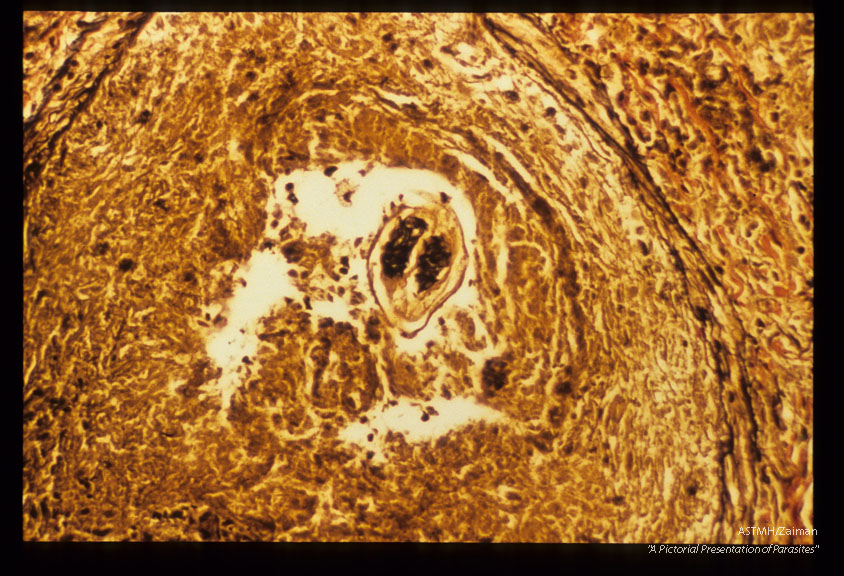

Adolescent filaria in pulmonary artery. Ipw and high power view. Elastic Berhoeff stain.

Description: Adolescent filaria in pulmonary artery. Ipw and high power view. Elastic Berhoeff stain.